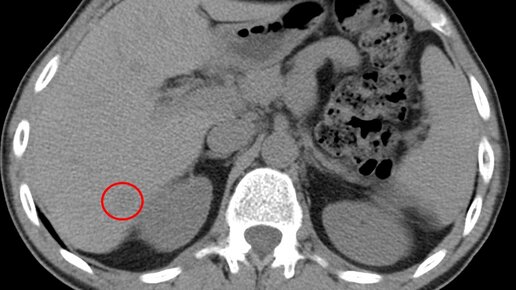

КТ брюшной полости является современным и точным рентгенологическим способом диагностики органов, расположенных в брюшной области. Во время обследования происходит томографическое, то есть, послойное сканирование исследуемой зоны. Современные мультспиральные томографы способны за один оборот сканера делать от 32 до 640 срезов, а мощный компьютер может создать трехмерные реконструкции всех анатомических структур области живота. Данные КТ снимков позволяют выявить воспалительные процессы и опухолевые изменения в костных и мягкотканных структурах...

КТ брюшной полости (Полное название мультиспиральная компьютерная томография брюшной полости) с контрастом применяют для обследования состояния органов, тканей и лимфатических узлов при подозрении на опухолевые или воспалительные заболевания...